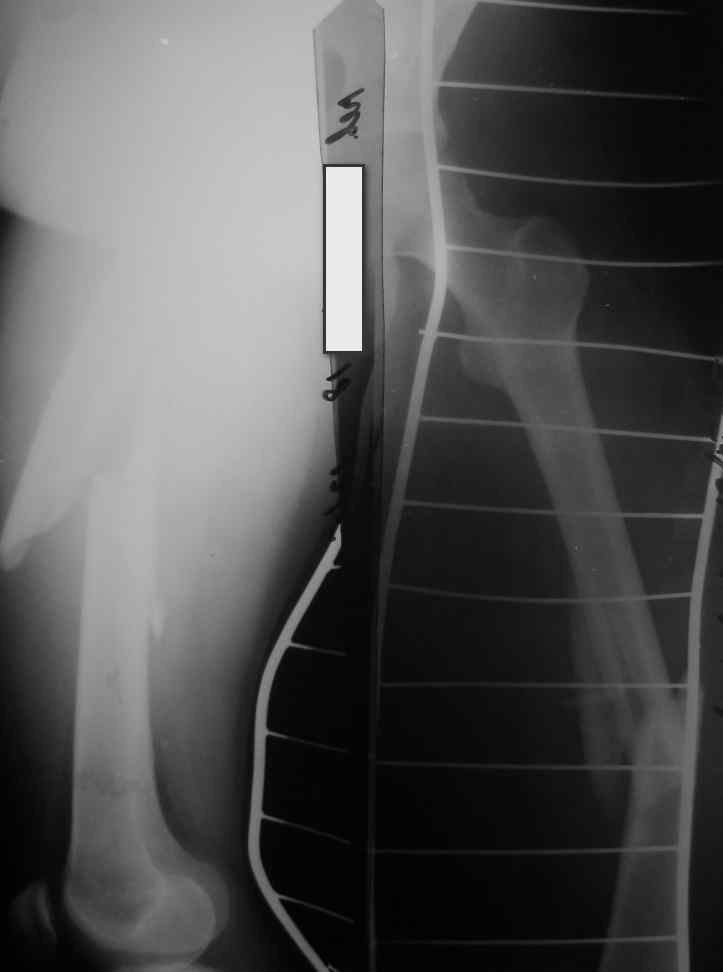

Перелом стержня, серкляж

Поступила молодая,маленькая девочка 18 лет с болями в левом бедре. Из истории:автодорожная травма в ноябре 2005 года, тогда же оперировалась данным способом. Проживает в селе и как правило в таких случаях выпала из поля зрения ведущего доктора.

По нашему мнению возможен реостеосинтез штифтом с рассверливанием более большого диаметра.Но возникают вопросы:

1.Убирать серкляж или нет если получится удалить отломки ChM закрыто.

2.Устранять деформацию бедра АВФ этапно или сразу одномоментно в ДРУ.

3.Блокирование - статическое или динмическое (либо статику на месяц а потом динамизация?)

4.Вопрос о костной пластике и туннелизации.